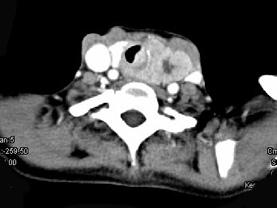

问题 女,50岁,左下颈部扪及一质硬、表面高低不平的包块,约半年,肿块逐渐增大,现感吞咽困难。如图所示CT诊断为 ( )

选项 A、甲状腺原发淋巴瘤 B、颈部神经鞘瘤 C、食管癌 D、喉癌 E、甲状腺癌

答案 E